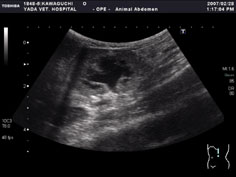

腹部エコー検査

腹部の臓器や組織、つまり肝臓や胆嚢、膵臓、腎臓、脾臓などの臓器、胃や腸、大腸などの消化管、さらに膀胱、前立腺、子宮どの検査をおこないます。腹部エコーは検査時に痛みもなく、リアルタイムで動きも観察できます。ただし、消化管内などにガスがあると観察できないこともあります。また、飼い主さんに理解してもらいやすくするため、3D合成することもあります。

左上段:犬・肝臓および胆嚢粘液症

右上段:猫・尿管閉塞による水腎症

左中段:犬・脾臓腫瘍

右中段:犬・ひも状異物による腸閉塞

左下段:猫・膀胱結石(3D合成画像)

右下段: 左の症例猫から摘出した結石 |